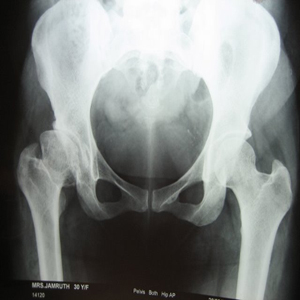

30 years old lady presented with complaint of pain right hip since 7 yrs and getting worse since 1 month. She is unable to walk and stand for a long time.

On examination she is having a painful limp, shortening of right lower limb, her hip movements are restricted and painful.

Xray showed evidence of old perthes disease and secondary osteoarthritis of right hip.

Hip Arthritis

In view of her young age , an uncemented Total Hip Replacement was carried out.

Hip Arthritis Uncemented Replacement

Post operative period was uneventful and she is walking painfree from 2nd post operative day .